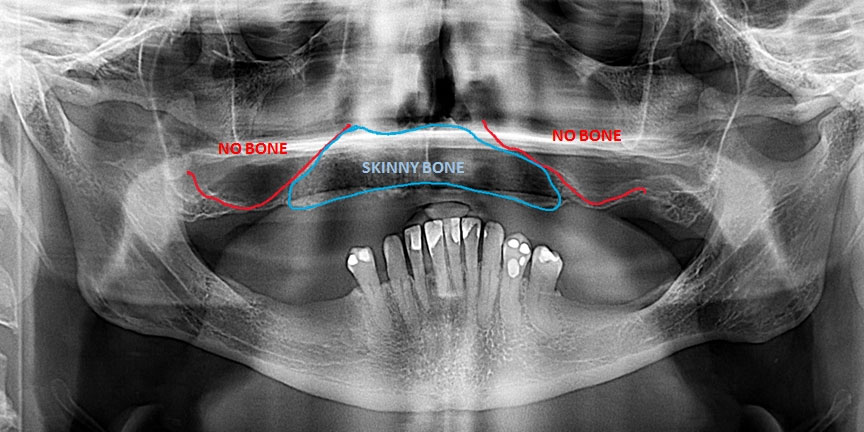

Severe Bone Loss